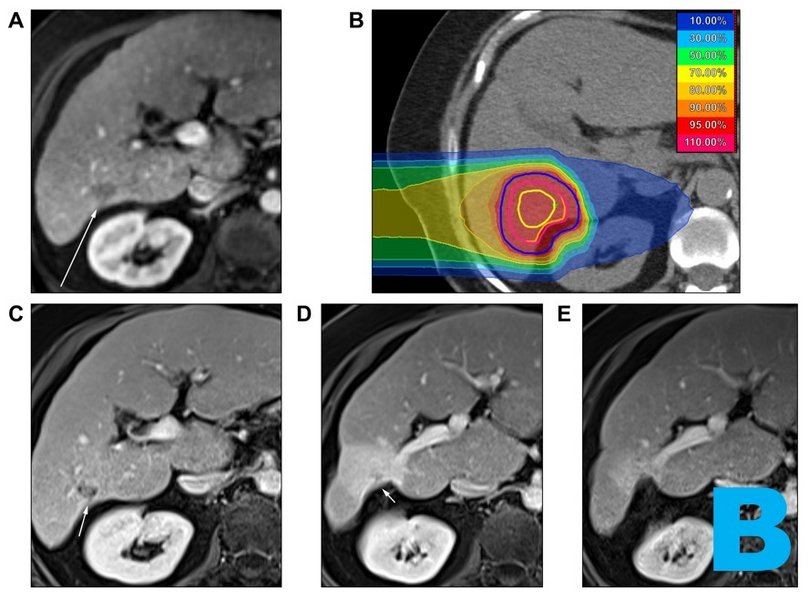

B

Images from PROMETHEUS. Patient with complete remission after CIRT. (A) before CIRT, (B) CIRT plan, (C) (D) (E) 1, 9 and 24 months after CIRT.